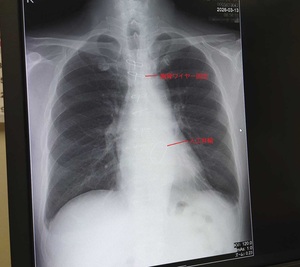

退院後初回(3/13(金))外来でのレントゲン写真

ガッチリ胸骨と緊結されてるけど咳き込んだり捻ると激痛w